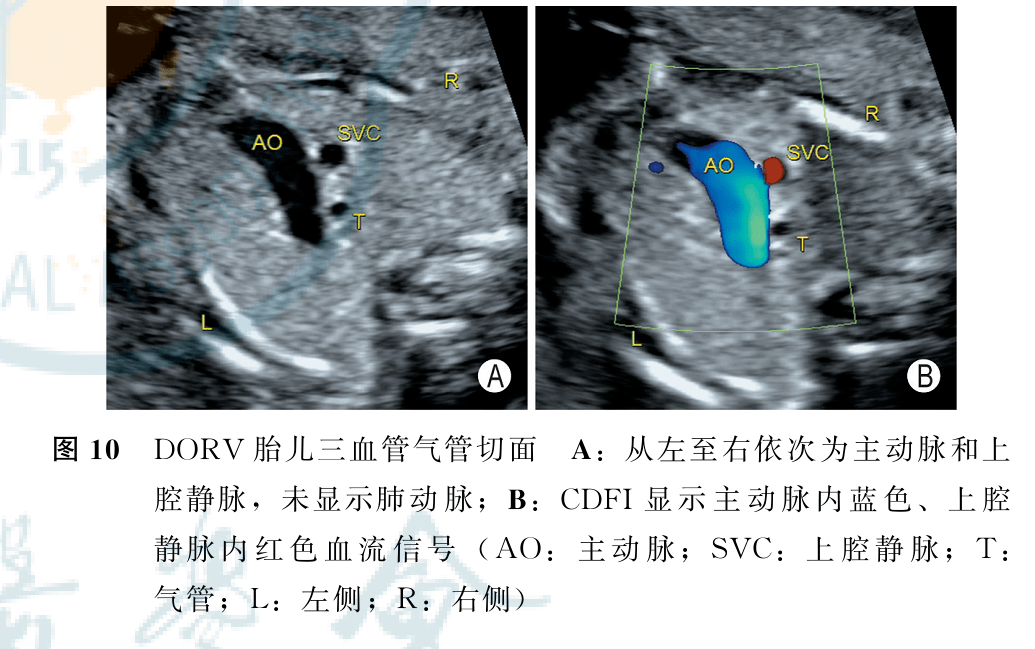

症和右室双出口超声检查中国专家共识(2022版)(二)_动脉_进行_分型